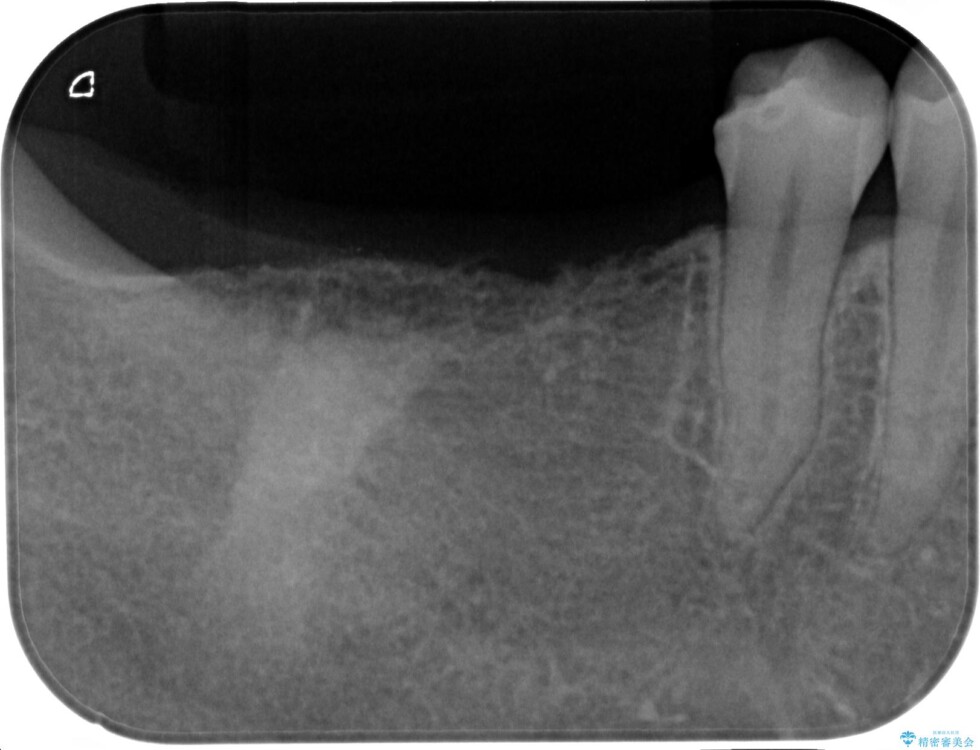

「1年前に抜歯した右下の奥歯にインプラントを入れたい」とのことで来院されました。

インプラント希望部位は右下第一大臼歯と第二大臼歯です。

しかし、噛み合わせの相手である右上の第二大臼歯が、長期間噛み合う歯がなかった影響で**挺出(歯が下に伸びてくる状態)してしまっており、このままではインプラントを埋入して被せもの(上部構造)を入れるためのスペースが不足している状態でした。

• 挺出歯を圧下してスペースを確保!目立たない部分矯正で下顎大臼歯にインプラント治療を実現 治療前画像